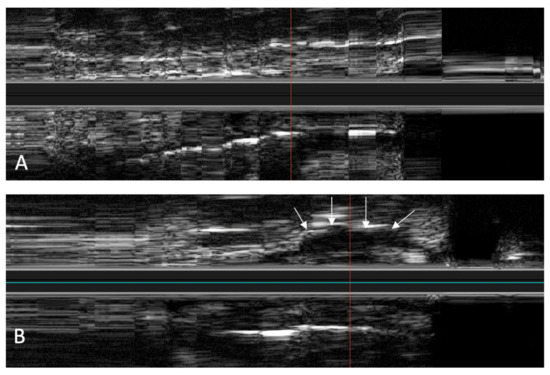

The IVUS provided a good image of the slit-formed shape of the ET (Figure 1) and the bony part with the isthmus (Figure 2) in the cross-section view. Bony structures and cartilage can be distinguished from the muscles and the Ostman fat pad. The signal transmission from the catheter to the tissue appeared to be good in all cases, even though the mucosal layer also caused some intense reflections. By flushing the ET with water (Figure 3), the lumen was more visible and became spindle shaped. Reflections at the mucosal layer were reduced.

Figure 4. Longitudinal image of the ET with the corresponding cross sections. (a) near the ET isthmus. (b) in the middle section of the ET. (c) near the pharyngeal ostium. Bone is marked with *. The bony structures represent consistent topographic landmarks. The cartilage of the ET shows low echogenicity (white arrows). Note that the dashed red line in the cross-sectional image represents the axis of the longitudinal image. The tip of the arrow points toward the lower part of the longitudinal image.